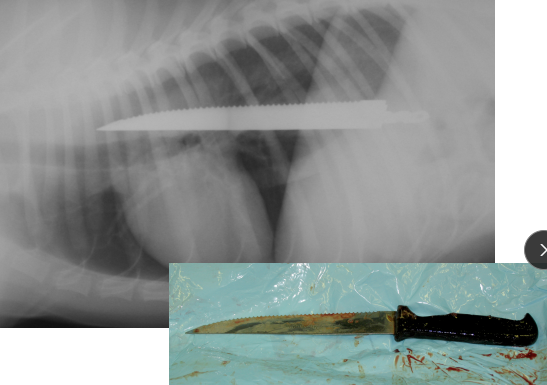

Esophageal Foreign Body

Et: located at cervical, thoracic inlet, base of heart, diaphragm

Sig: young

Cs: acute regurg, dysphagia, gagging, salivation

Dt: rads, endoscopy

Tx: urgent endoscopic removal or surgery

Comp: perforation, esophagitis, stricture, aspiration pneumonia

Esophageal Perforation

Et: Air in mediastinum or pleural space

Cs: peri-esophageal swelling, pain, resp distress

Dt: Serial rads

Tx: NG tube feeding, Antibiotics, fluids: heals w/ symptomatic therapy

Sx if Large